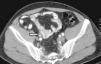

Presentación de caso clínicoSe trata de paciente masculino de 60 años de edad, el cual acude al servicio de urgencias con cuadro de hematuria macroscópica, indolora, no formadora de coágulos. Dentro de su anamnesis refiere nefrectomía radical izquierda por tumor renal, encontrando en el reporte histopatológico tumor de 9cm con necrosis central que invade la cápsula renal. No acudió a sus citas de revisión posterior a la intervención quirúrgica. En la exploración física abdominal, con sitio de cicatriz de lumbotomía izquierda, sin datos de visceromegalias ni puntos doloroso. Los resultados de laboratorio se encuentra: hemoglobina 16g/dl, plaquetas 167,000, creatinina 1mg/dl, BT 1.65mg/dl, BD 0.5mg/dl, BI 1.07mg/dl, fosfatasa alcalina 134 U/l. Se realiza una tomografía simple y contrastada de abdomen y pelvis, observando ausencia quirúrgica del riñón izquierdo, ectasia ureteropiélica derecha con lesión ocupante en el uréter derecho, redondeada, de 2×2cm de diámetro a nivel del cruce con vasos iliacos, con densidad de 10-20 UH y que refuerza en fase contrastada a 50-60 UH (figs. 1 y 2).